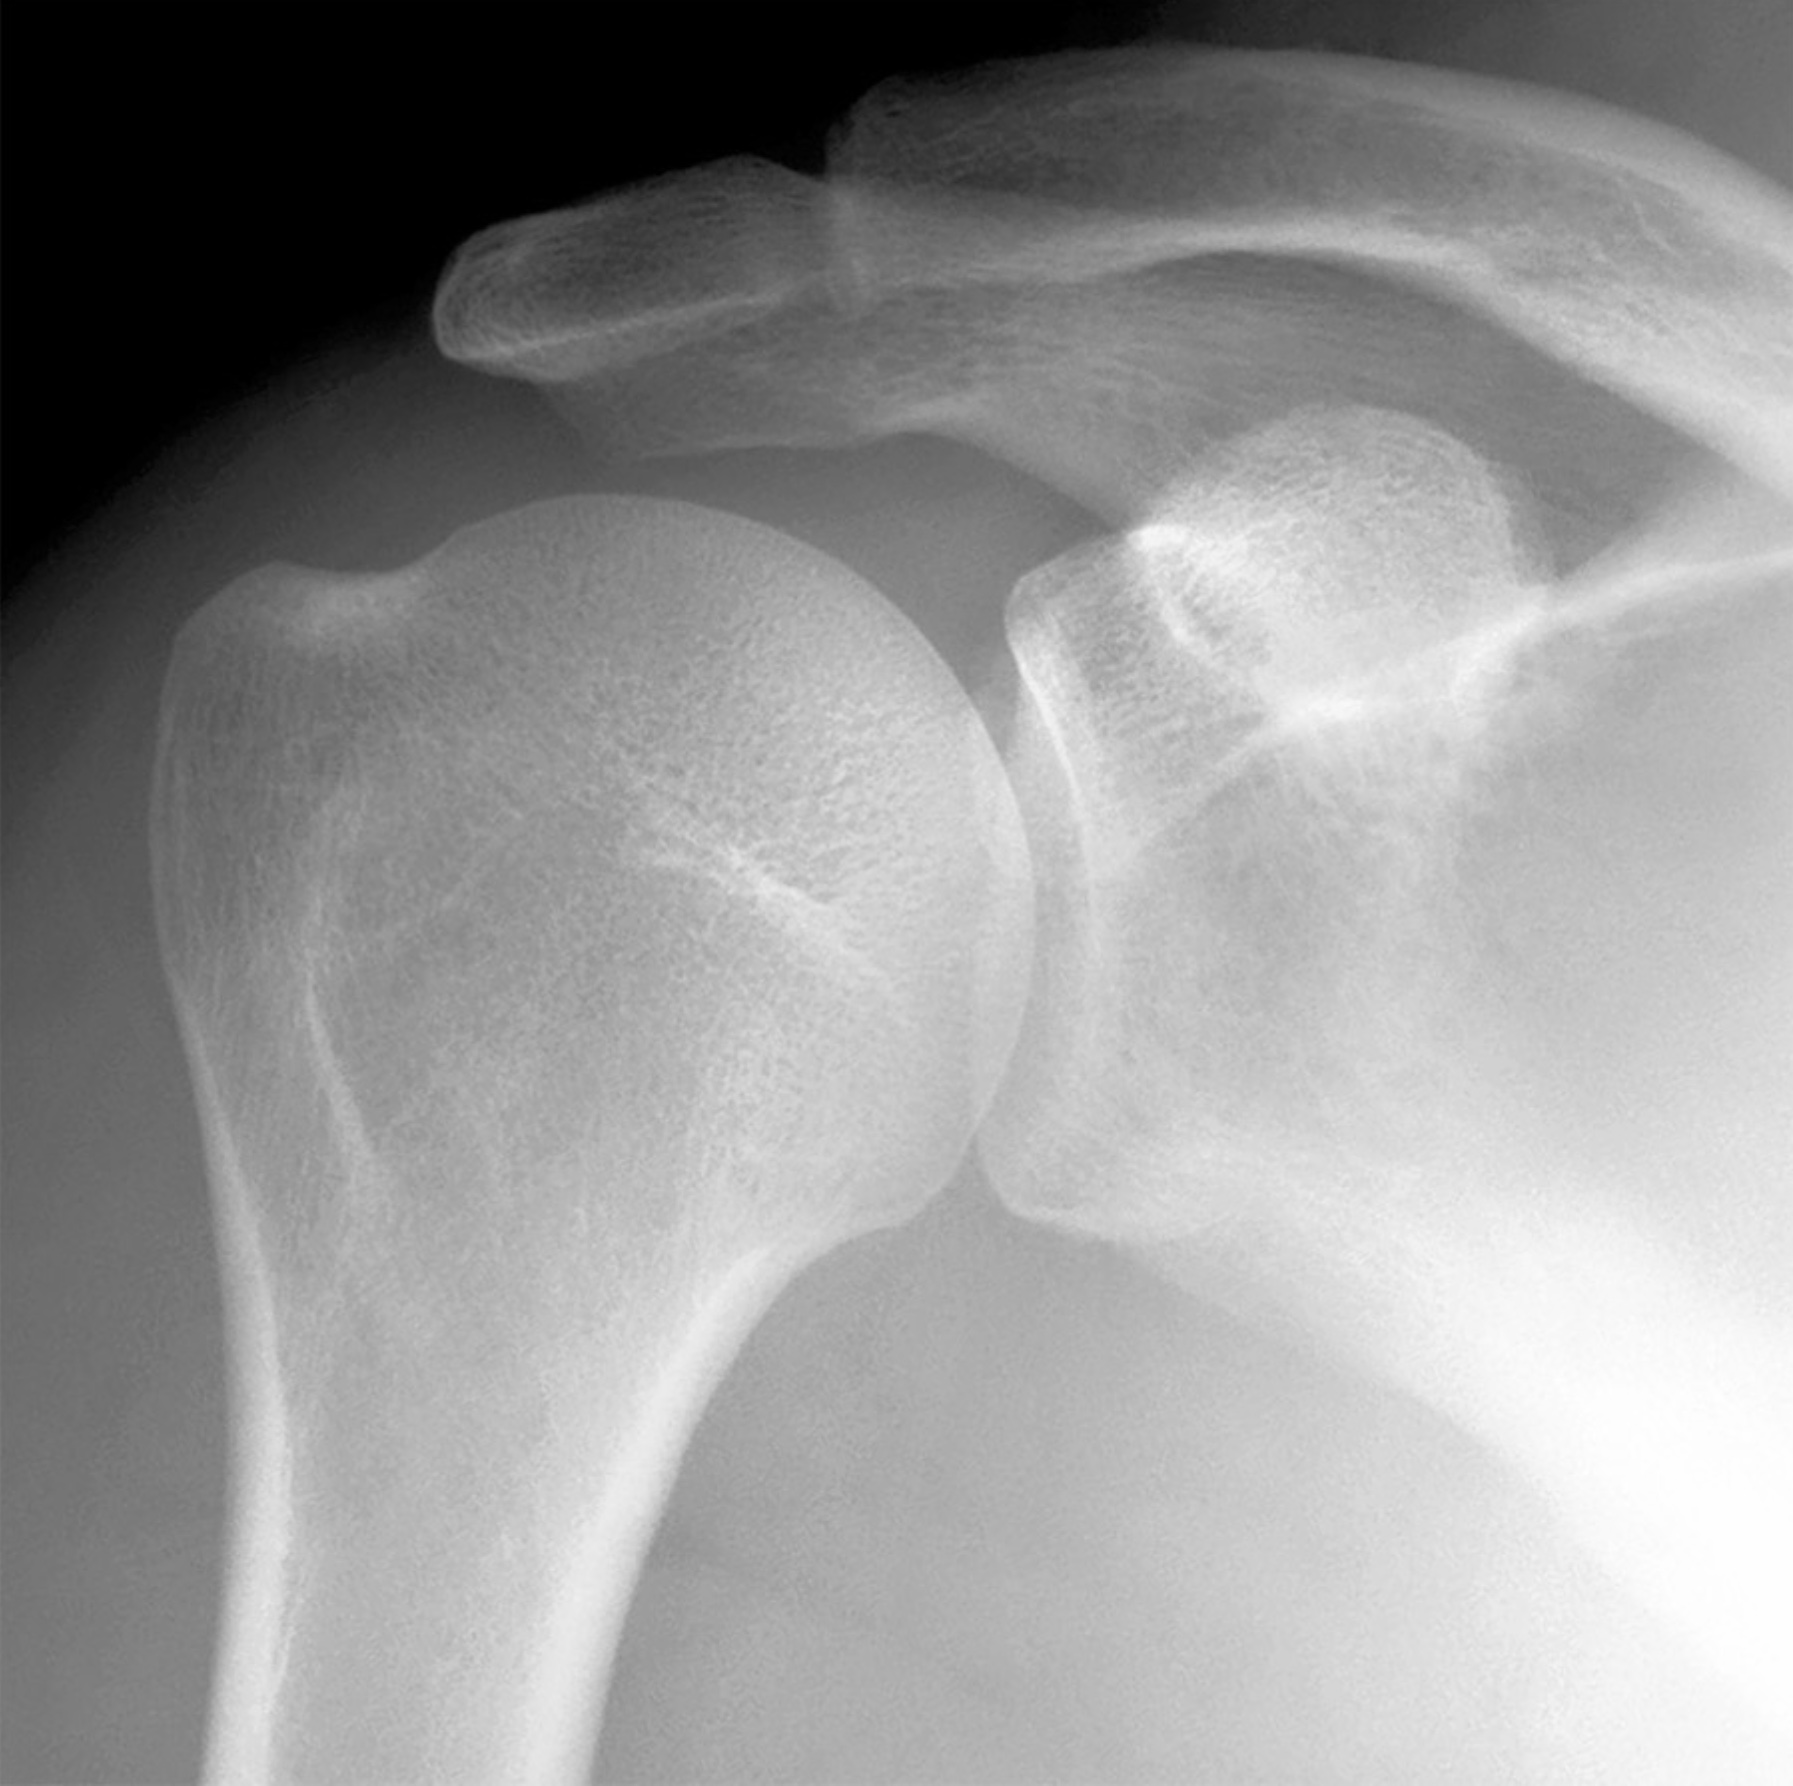

1. A shoulder separation and a shoulder dislocation occur at different joints. Review the anatomy of the acromioclavicular joint. Include bones, articulations, ligaments, capsules, cavities, movements and limitations of movement, and relationships.

2. The shoulder joint has extreme mobility paired with inherent instability. Review the anatomy of the glenohumeral joint. Include bones, articulations, ligaments, capsules, cavities, contents, muscles, movements and limitations of movements, vasculature, lymphatic drainage, innervation, and relationships.

1. The clavicle is suspended from above by the trapezius and sternocleidomastoid muscles. Thus, a downward blow to the lateral margin of the acromion might rupture the acromioclavicular, trapezoid, and conoid ligaments resulting in a shoulder separation. (True)